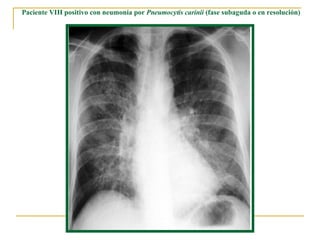

Paciente VIH positivo con neumonía por  Pneumocytis carinii  (fase subaguda o en resolución)

Neumonía por  Pneumocystitis carinii.  Patrón pulmonar intersticial bilateral.